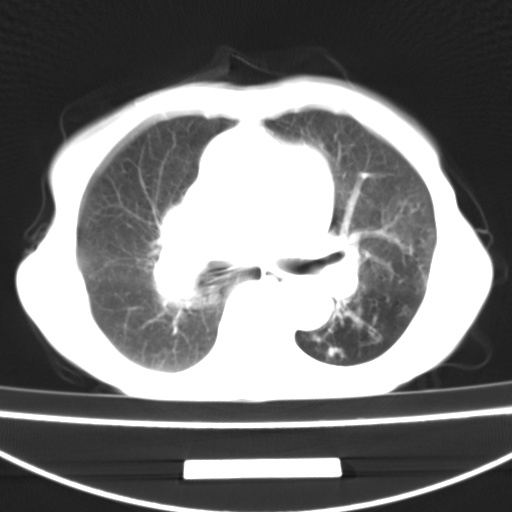

患者 女 67岁,反复咳嗽咳痰2年,加重伴喘及双下肢浮肿1月

诸大血管及f肺门血管增粗迂曲.左下肺多发薄壁空腔影.部分非也透亮度增高.薄曾扫描可区分肺气肿类型.考虑1.慢性支气管炎 2.左下肺支气管扩张 3.肺气肿 4 肺动脉高压5.是否有先心病病史

考虑1.慢性支气管炎 2.左下肺支气管扩张 3.肺气肿 4 肺动脉高压

慢支炎、肺气肿、双肺感染、左下囊状支扩。

慢支、肺气肿、肺动脉高压;左下肺囊状支扩并粘液栓形成。